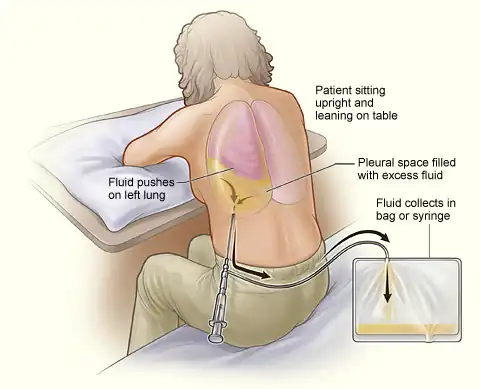

Thoracentesis /ˌθɔːrəsɪnˈtiːsɪs/, also known as thoracocentesis (from Greek θώραξ (thōrax, GEN thōrakos) 'chest, thorax' and κέντησις (kentēsis) 'pricking, puncture'), pleural tap, needle thoracostomy, or needle decompression (often used term), is an invasive medical procedure to remove fluid or air from the pleural space for diagnostic or therapeutic purposes. A cannula, or hollow needle, is carefully introduced into the thorax, generally after administration of local anesthesia. The procedure was first performed by Morrill Wyman in 1850 and then described by Henry Ingersoll Bowditch in 1852.[1]

The recommended location varies depending upon the source. Some sources recommend the midaxillary line, in the eighth, ninth, or tenth intercostal space.[2] Whenever possible, the procedure should be performed under ultrasound guidance, which has shown to reduce complications.[3][4][5]

This procedure is indicated when unexplained fluid accumulates in the chest cavity outside the lung. In more than 90% of cases, analysis of pleural fluid yields clinically useful information. If a large amount of fluid is present, then this procedure can also be used therapeutically to remove that fluid and improve patient comfort and lung function.

When cardiopulmonary status is compromised (i.e. when the fluid or air has its repercussions on the function of heart and lungs), due to air (significant pneumothorax), fluid (pleural fluid) or blood (hemothorax) outside the lung, then this procedure is usually replaced with tube thoracostomy, the placement of a large tube in the pleural space.

Relative contraindications include cases in which the site of insertion has known bullous emphysema, use of positive end-expiratory pressure (PEEP, see mechanical ventilation) and only one functioning lung (due to diminished reserve). Traditional expert opinion suggests that the aspiration should not exceed 1 L to avoid the possible development of pulmonary edema, but this recommendation is uncertain as the volume removed does not correlate well with this complication.[5]

Major complications are pneumothorax (3–30%), hemopneumothorax, hemorrhage, hypotension (low blood pressure due to a vasovagal response) and reexpansion pulmonary edema.

Minor complications include a dry tap (no fluid return), subcutaneous hematoma or seroma, anxiety, dyspnea and cough (after removing large volume of fluid).